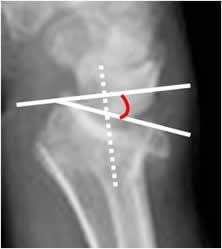

La inclinación volar:

Trazado en la Rx lateral. Angulo formado entre la perpendicular al eje del radio y una línea que une su extremo anterior y posterior. El valor normal es entre 0 y 22º (12). Cualquier valor negativo es patológico. (13). (Fig 49 y 50).

Fig 49. Inclinación volar.

Rx lateral de muñeca. Angulo formado entre la perpendicular al eje del radio y una línea que une la parte anterior y posterior del radio distal.

Fig 50. Fractura de radio.

Rx lateral. Fractura deprimida del radio distal, con inversión del ángulo de inclinación volar.